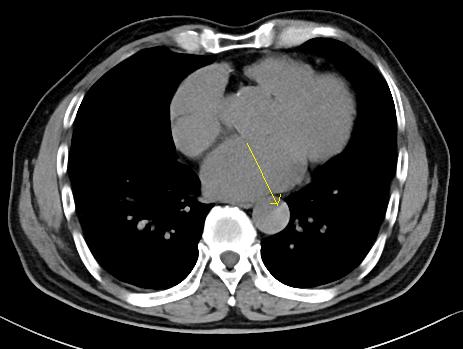

下图的胸部CT平扫,有什么致命的问题?

图7

仔细一看,主动脉里面有线样阴影!并且,线样阴影两边的密度一高一低!

图8

增强CT一看,主动脉夹层,密度相对高的是流动的血液!

图9